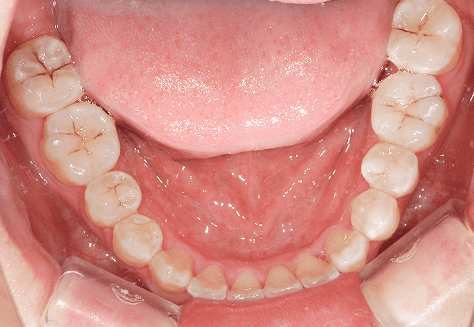

S.K

治療前

治療後

主訴

歯が重なっていて気になる。前歯が出ていて唇が閉じにくい。ハミガキがしにくい。

診断

上顎前突・叢生

年齢/性別

20代/男性

抜歯部位

上下第三大臼歯

使用装置

上下インビザライン

保定装置

上下ビベラリテーナー

料金

初回資料採得・・・・・・・30,000円

診断料・・・・・・・・・・33,000円

動的治療終了時資料採得・・5,500円 -

基本料金

990,000円

診察料金

1,100円×33回

治療期間

3年5カ月